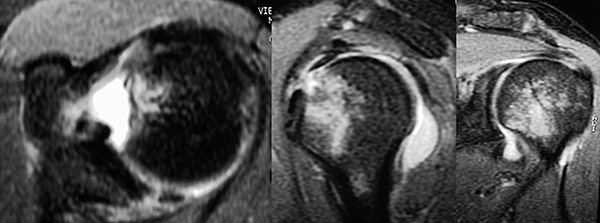

A continuación se realizó la reinserción anatómica del tendón del subescapular y cápsula, mediante 1 anclaje óseo similar a los utilizados, con el objetivo de evitar una desinserción durante el periodo de rehabilitación. En el postoperatorio se indicó inmovilización con un cabestrillo modificado manteniendo el miembro en rotación neutra, limitando la rotación interna del brazo por 3 semanas para evitar contracturas con pérdidas de la rotación externa. Posteriormente se permitió ejercicios pendulares de movilidad pasiva y activos asistidos en forma progresiva. A la 12ª semana el paciente alcanzo 90 grados de abducción y flexo extensión completa sin evidencia de inestabilidad. Al año de evolución postoperatorio, movilidad completa, con un hombro estable, retornando a sus actividades deportivas (Fig. 10). Se evaluó al paciente a los 60 meses con el “Score” del D.A.S.H y Constant. Se obtuvo una recuperación funcional satisfactoria con déficit funcional de rotación externa de 10º. Se corroboró consolidación del fragmento osteo-condral mediante la utilización de la T.A.C. y Rx. simple (Fig. 11).

Figura 10: Rx. AP y Vuelo pájaro: Evaluación radiológica a las 12 semanas del post-op.

Figura 11: Evaluación funcional a los 5 años de post-op. Evaluación Radiográfica y Tomográfica: Consolidación del fragmento osteo-condral, sin signos de artrosis. Evaluación de la posición del arpón en la reparación del Bankart Reverso.

La reparación anatómica de esta lesión (Bankart reversa + fractura osteocondral humeral anterior) mediante el procedimiento artroscópico y fijación interna estable del fragmento osteocondral, ha demostrado tener un resultado subjetivo y objetivo satisfactorio a los cinco años de seguimiento, sin evidencias de lesiones degenerativas articulares.